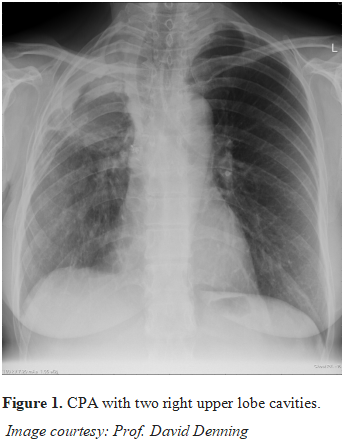

Led by Inderpaul Sehgal of Postgraduate Institute of Medical Education and Research, Chandigarh, this single-centre, prospective, open-label, superiority trial enrolled treatment-naive adults aged 18 years or older with chronic cavitary or chronic fibrosing pulmonary aspergillosis. Participants were randomly assigned 1:1 to receive 200 mg twice daily oral itraconazole or oral voriconazole for 6 months. The primary and secondary outcomes were the proportion of participants achieving a favourable response at 6 months and safety analyses.